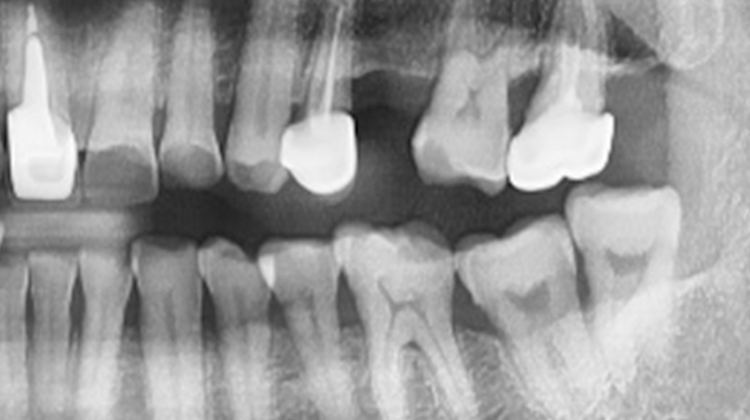

신경 손상의 위험

사랑니의 수술 난이도

턱뼈 손상의 위험

- 사랑니 발치 시 신경 손상과 턱뼈 손상의

위험이 있으므로 주의가 필요합니다. - 사랑니의 뿌리가 신경에 가까이 있거나

턱뼈 깊숙이 매복된 경우, 발치 전 정밀 검사를 통해 신경과 턱뼈의 위치를 철저히 분석해야 합니다. - 특히 매복 사랑니는 잇몸 절개, 치아 분할, 뼈 삭제 등의 추가 수술이 필요할 수 있으며, 종양 발생 위험도 있어 신중한 접근이 요구됩니다.